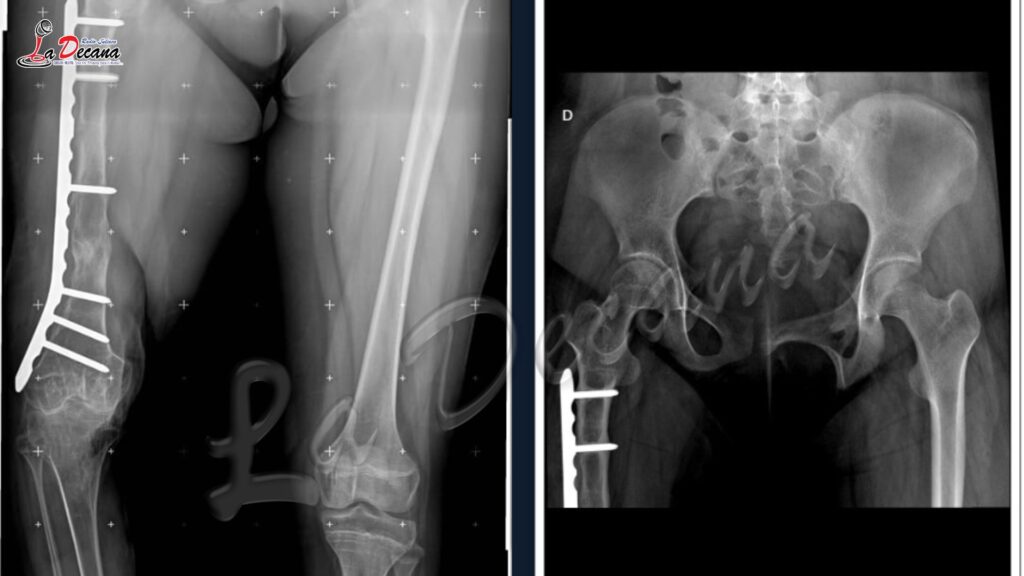

Desde entonces, la familia ha atravesado una verdadera odisea. La menor fue trasladada a Lima, donde se le practicaron 26 cirugías en un esfuerzo por reconstruir los graves daños que sufrió. Sin embargo, pese a la intervención de diversos especialistas, las secuelas persisten y su salud continúa deteriorándose.

Ante la falta de una solución definitiva en el país, Turpo Huarecallo logró contactar a especialistas en una clínica privada de Madrid, España, quienes evaluaron el caso y confirmaron que existe una alta probabilidad de éxito en una intervención reconstructiva compleja, además de una segunda cirugía necesaria en la pierna derecha.

La salud de la adolescente se encuentra en riesgo. Según relata su padre, en los últimos meses ha sufrido infecciones urinarias constantes, dolores severos y complicaciones en su sistema digestivo debido al consumo prolongado de medicación. A ello se suma la necesidad urgente de reconstrucción ósea y ligamentaria, pues en su pierna derecha se le tuvieron que retirar 10 centímetros de hueso por infección; posteriormente se le realizó un alargamiento de 5 centímetros, pero aún requiere una intervención definitiva.